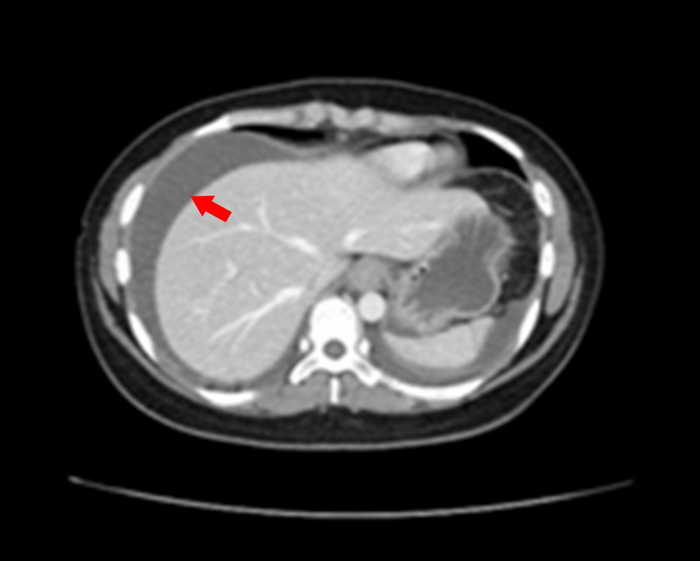

圖二:患者腹部電腦斷層(箭頭處是積水) 。